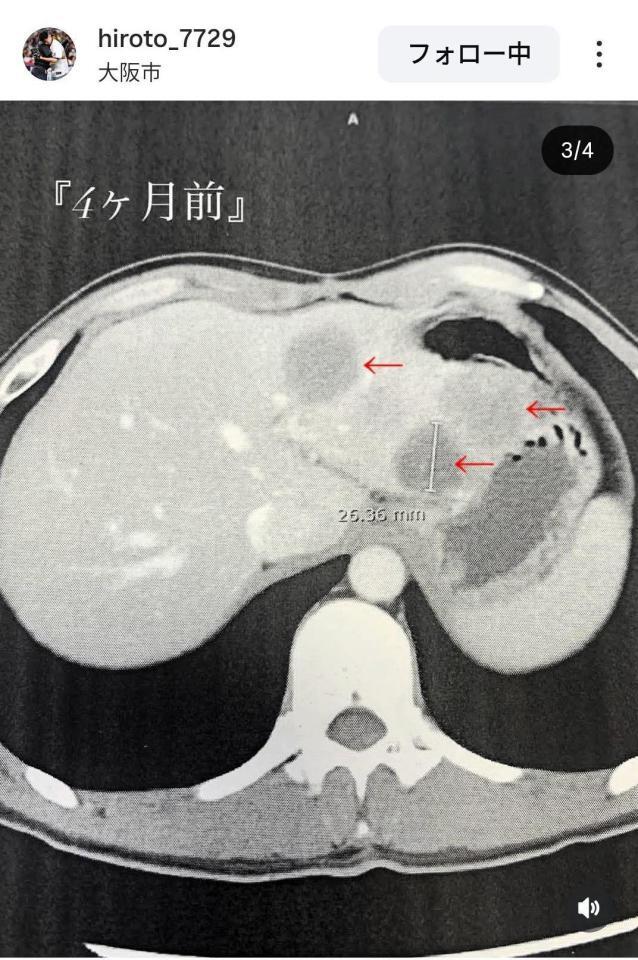

元大阪桐蔭野球部 希少がん闘病中の福森大翔さんが経過報告「このままでは胃と大腸もまずいと」4カ月前との画像比較「最後は勝つ!」